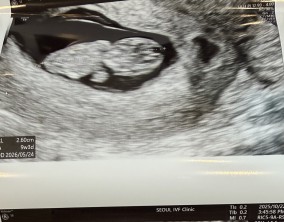

눈물로 실감한 아홉 번째 주

이경훈 원장님은 검사를 통해 나온 수치와 결과에 대해 자세히 설명해 주시고, 상황에 맞는 여러 방법을 함께 제시해 주셔서 큰 신뢰와 감사함을 느꼈습니다. 불안을 혼자 짊어지…